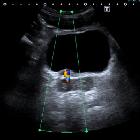

Twinkling artifact is seen with color flow Doppler ultrasound . It occurs as a focus of alternating colors on Doppler signal behind a reflective object (such as a calculus), which gives the appearance of turbulent blood flow . It appears with or without an associated color comet-tail artifact .

Twinkling artifact is more sensitive for detection of small stones (e.g. urolithiasis, cholelithiasis) than is acoustic shadowing. It is most pronounced when the reflecting surface is rough and highly dependent on machine setting:

The presence of renal twinkling artifact on sonography has a high positive predictive value (78%) for the presence of nephrolithiasis at unenhanced CT .